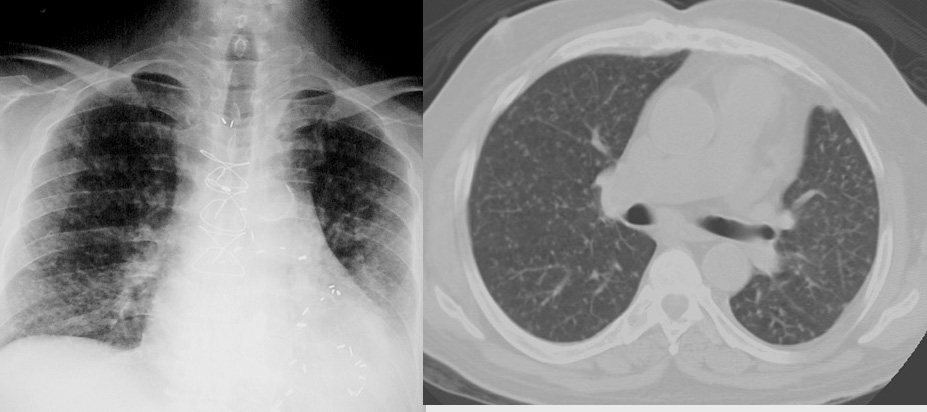

Widespread bilateral <5 mm nodules. Patient has had coronary bypass surgery and has cardiomegaly . CT from a different case shows widespread bilateral nodules less than 6 mm in diameter.